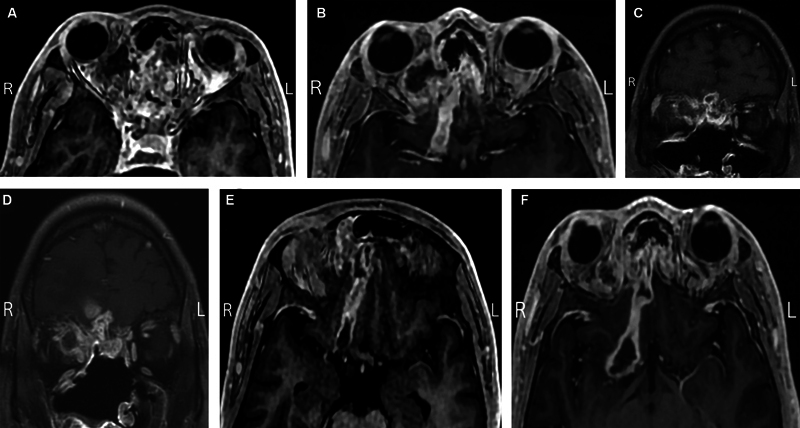

本病例报告一例29岁男性糖尿病患者并发鼻-眶-脑毛霉菌病(ROCM),经两性霉素B脂体眶内注射成功治疗。尽管紧急内镜清创,患者的疾病在颅内和眶内进展,但他拒绝进一步的手术干预。随后,由于急性视力迅速丧失,我们开始经皮球后两性霉素B (TRAMB)注射。注射后,尽管颅内进展,但视力、运动和眶内真菌负荷均有所改善。本报告强调了施用TRAMB治疗侵袭性真菌感染的益处,并探讨了其有效性背后的机制,特别是在全球保存方面。通过靶向血液供应相对稳定的区域的感染,TRAMB降低了手术难度并改善了总体结果。

This case report presents a 29-year-old male with diabetes mellitus who developed rhino-orbito-cerebral mucormycosis (ROCM) that was successfully treated with liposomal amphotericin B orbital injections. Despite emergent endoscopic debridement, the patient's disease progressed intracranially and intraorbitally, but he declined further surgical intervention. Subsequently, due to rapid acute vision loss, we initiated transcutaneous retrobulbar amphotericin B (TRAMB) injections. Following these injections, visual acuity, motility, and intraorbital fungal burden improved despite intracranial progression. This report highlights the benefits of TRAMB administration in aggressive fungal infections and explores the mechanisms behind its effectiveness, particularly in globe preservation. By targeting the infection in an area with a relatively robust blood supply, TRAMB reduces surgical difficulty and improves overall outcomes.